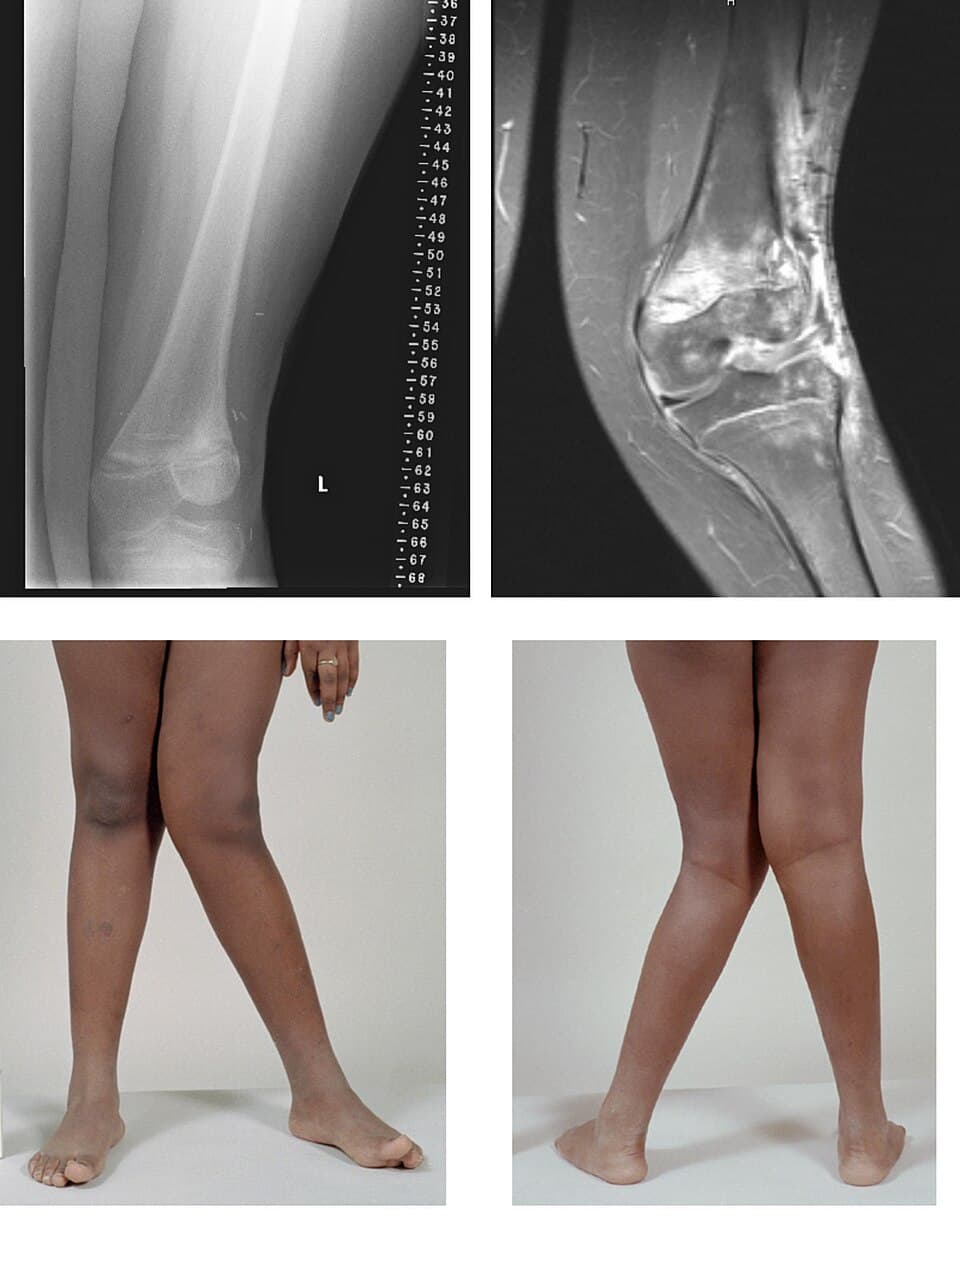

Genu valgum, commonly called "knock-knee", is a condition in which the knees angle in and touch each other when the legs are straightened. Individuals with severe valgus deformities are typically unable to touch their feet together while simultaneously straightening the legs. The term originates from the Latin genu, 'knee', and valgus which means "bent outwards", but is also used to describe the distal portion of the knee joint which bends outwards and thus the proximal portion seems to be bent inwards. Mild genu valgum is diagnosed when a person standing upright with the feet touching also shows the knees touching. It can be seen in children from ages 2 to 5, and is often corrected naturally as children grow. The condition may continue or worsen with age, particularly when it is the result of a disease, such as rickets. Idiopathic genu valgum is a form that is either congenital or has no known cause. Other systemic conditions may be associated, such as Schnyder crystalline corneal dystrophy, an autosomal dominant condition frequently reported with hyperlipidemia. Genu valgum can arise from a variety of causes including nutritional, genetic, traumatic, idiopathic or physiologic and infectious. Nutritional rickets is an important cause of childhood genu valgum or knock knees in some parts of the world. Nutritional rickets arises from unhealthy life style habits as insufficient exposure to sun light which is the main source of vitamin D. Insufficient dietary intake of calcium is another contributing factor. Genu valgum may arise from rickets caused by genetic abnormalities, called vitamin D-resistant rickets or X-linked hypophosphatemia. Osteochondrodysplasia are a variable group of genetic bone diseases or genetic skeletal dysplasias that present with generalized bone deformities involving all extremities and the spine. Genu valgum or knock knees is one of the known skeletal manifestations of Osteochondrodysplasias. A complete bone X-ray survey is mandatory to reach a definitive diagnosis.